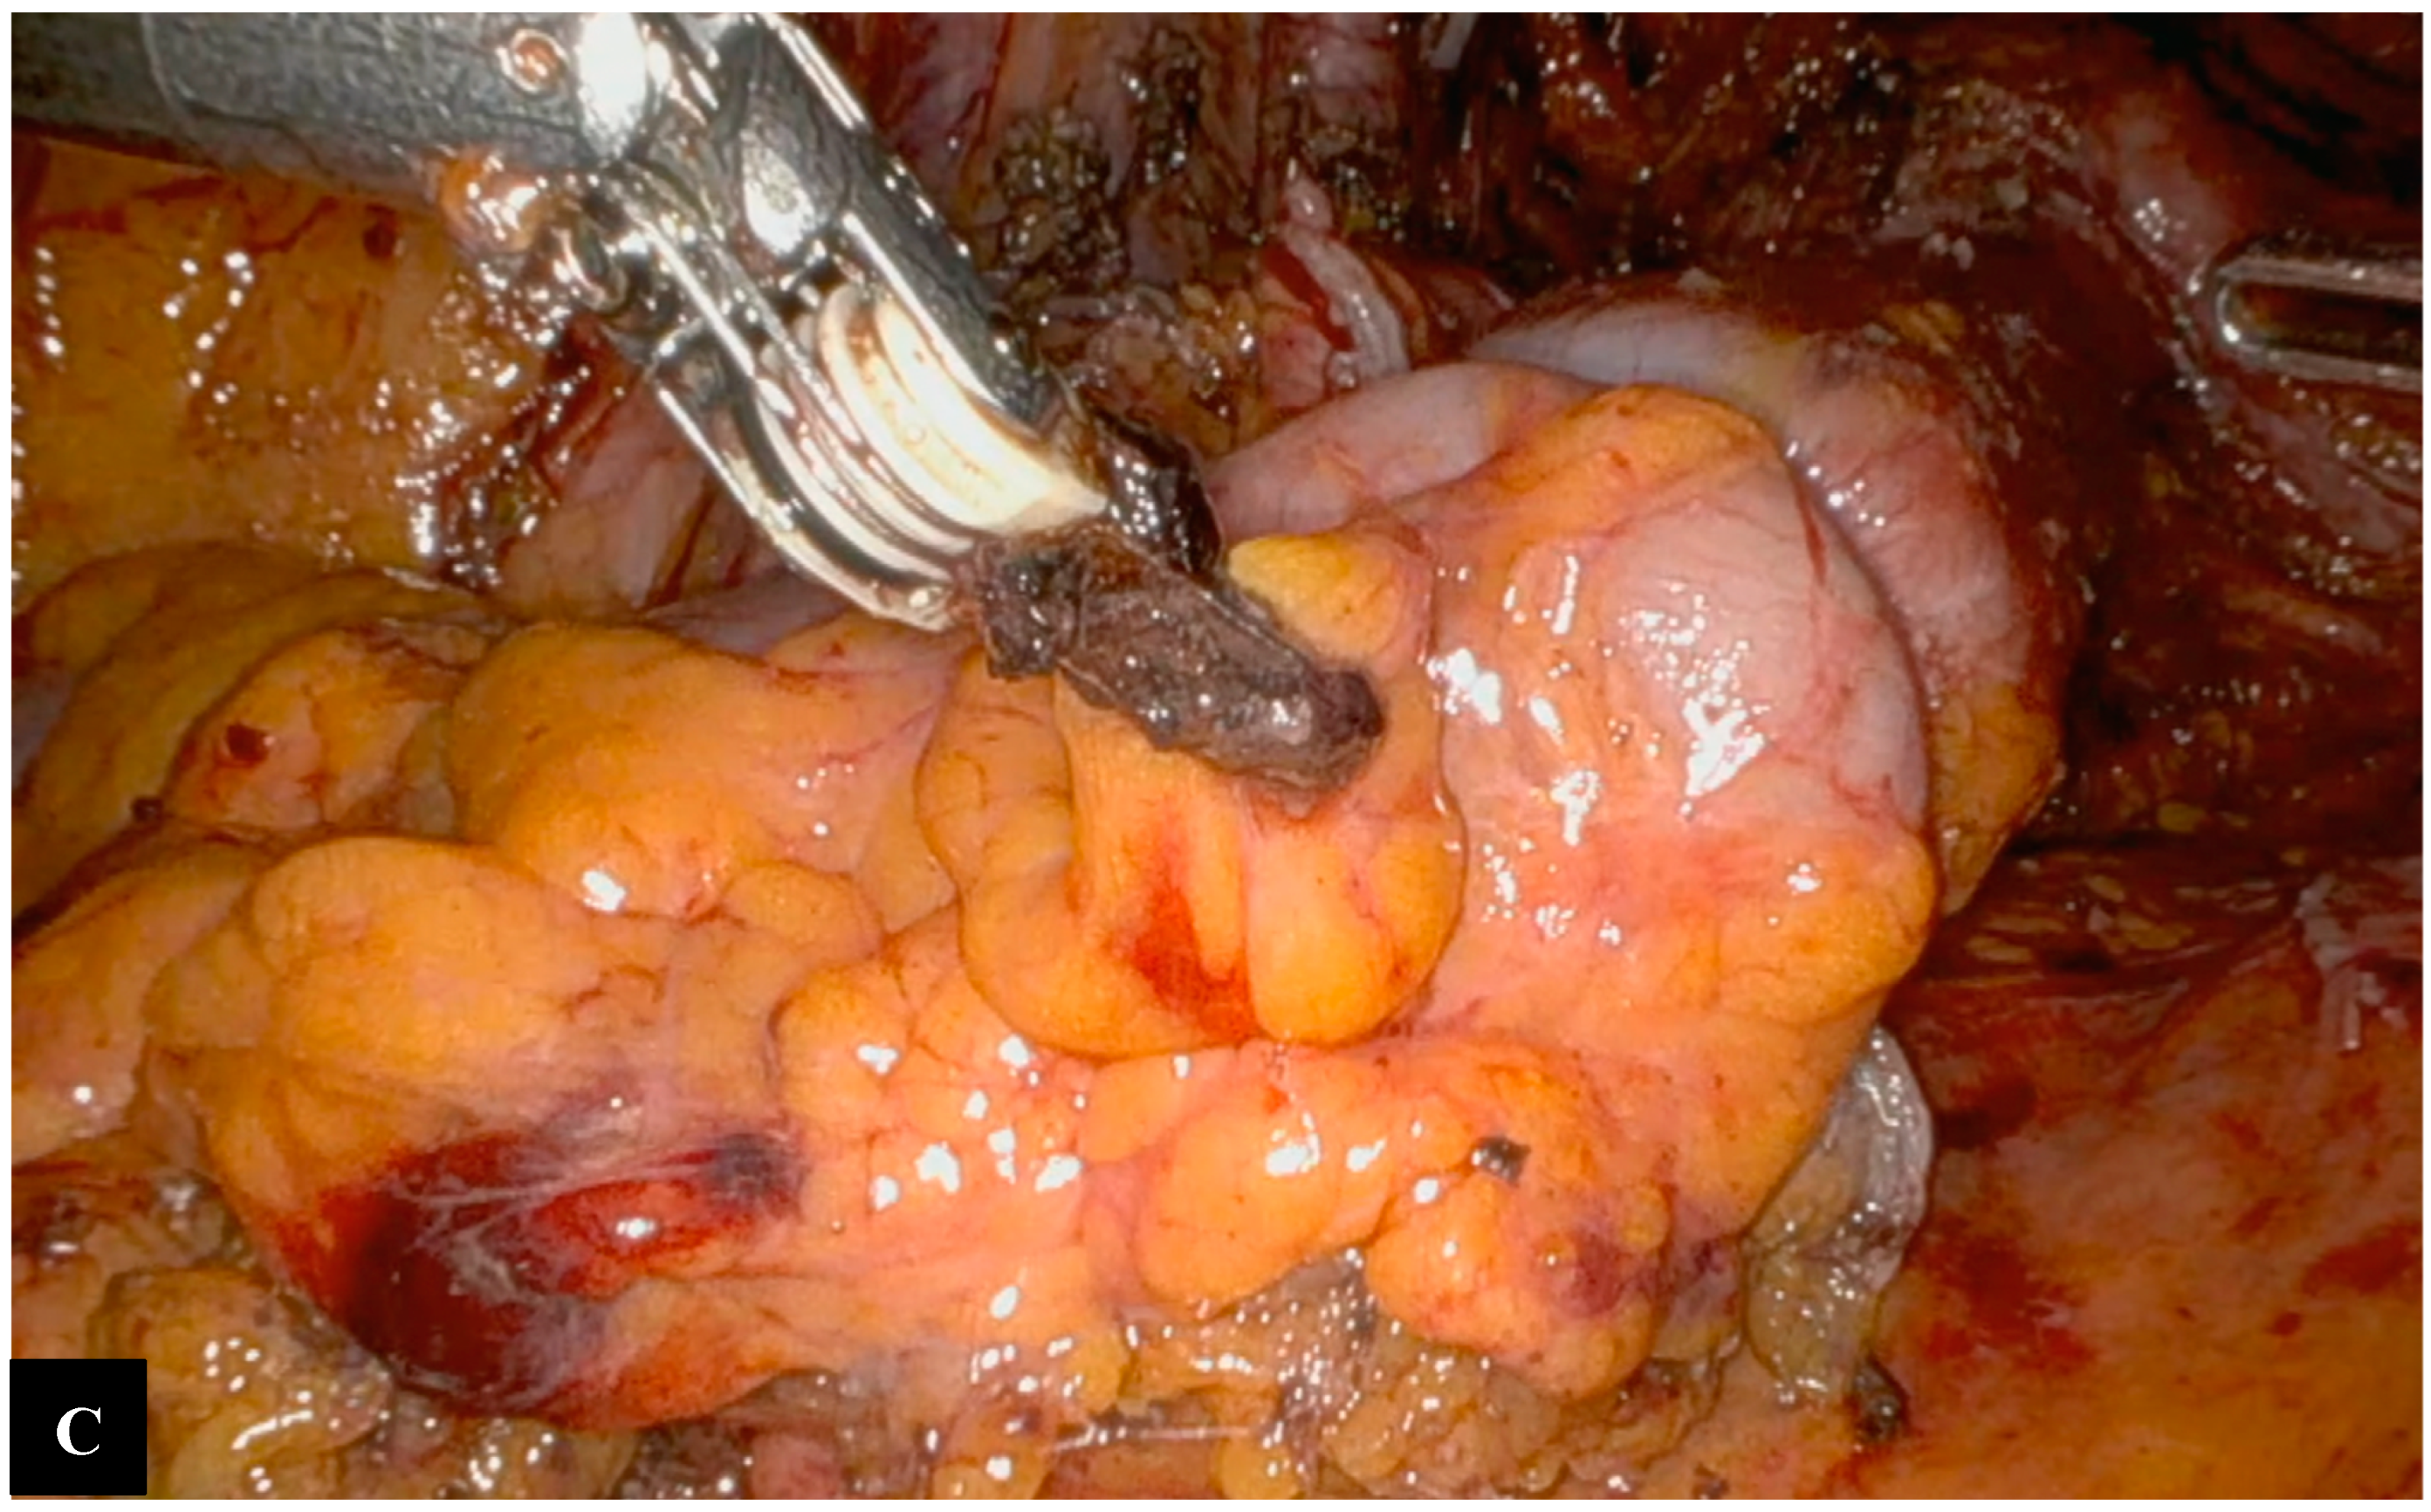

Operative Technique